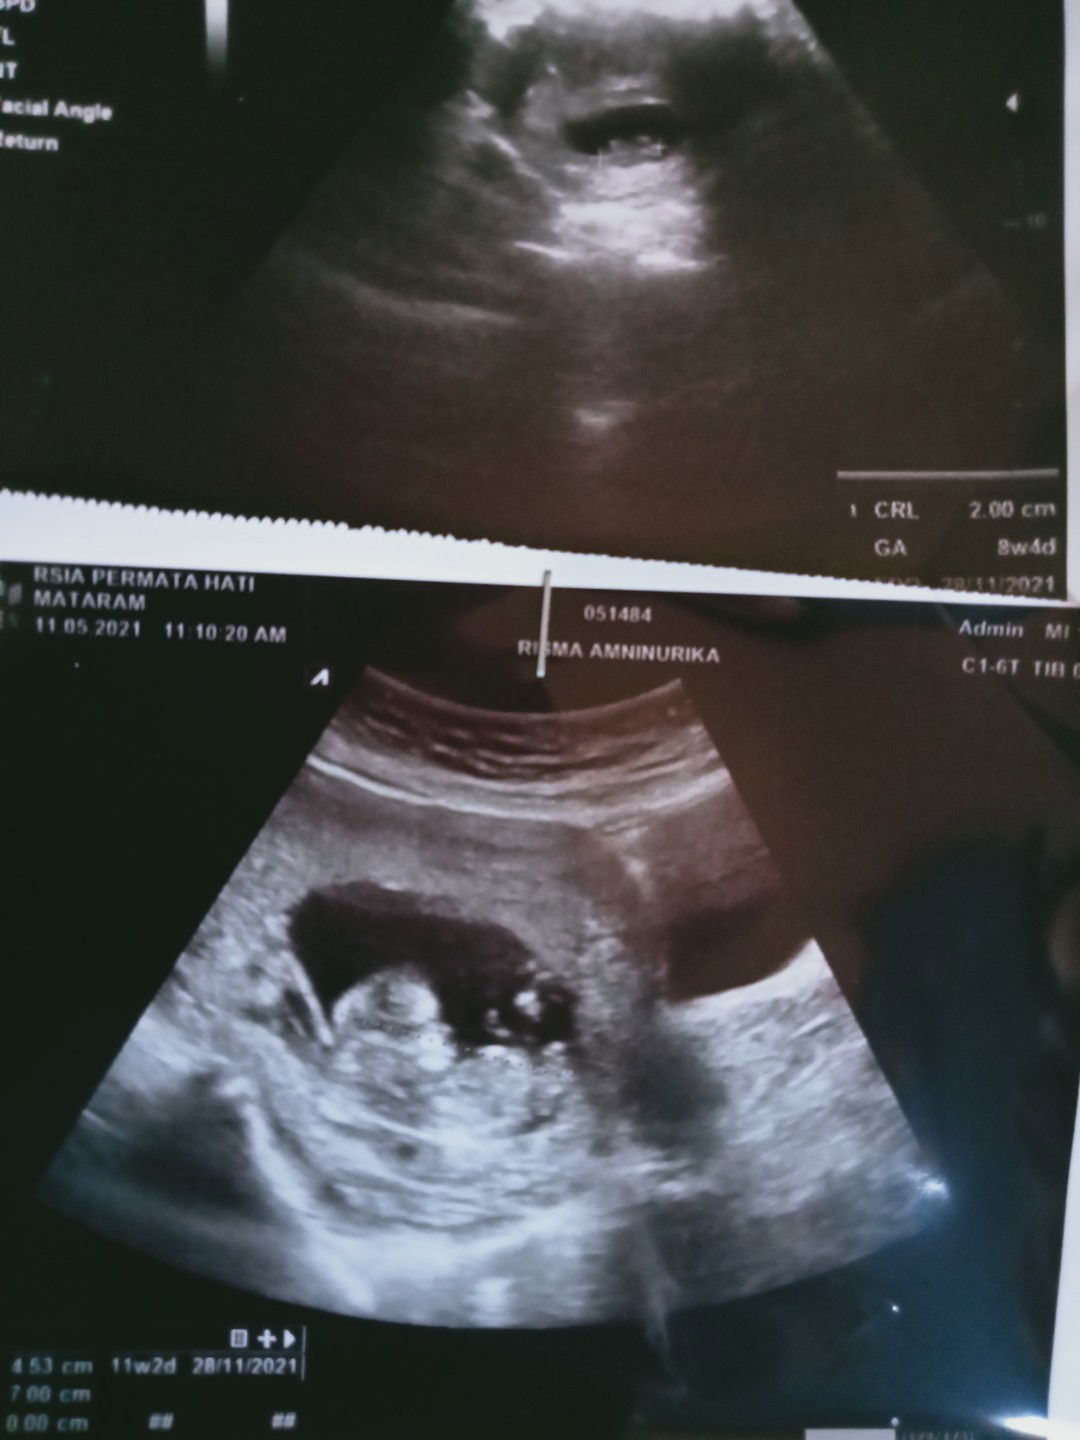

Bismillah aku lagi hamil anak pertama TM 1 Semoga selalu sehat.Aamiin